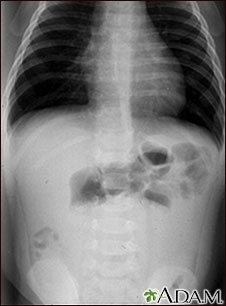

Radiografía de una invaginación

Esta radiografía abdominal muestra una condición en la que un asa intestinal se ha deslizado de otra sección del intestino (invaginación), causando hinchazón, reducción del flujo sanguíneo, obstrucción y daño a los tejidos. La invaginación requiere tratamiento de emergencia (enema de bario o cirugía) para evitar muerte del tejido intestinal (necrosis), perforación intestinal, peritonitis y la muerte del paciente.